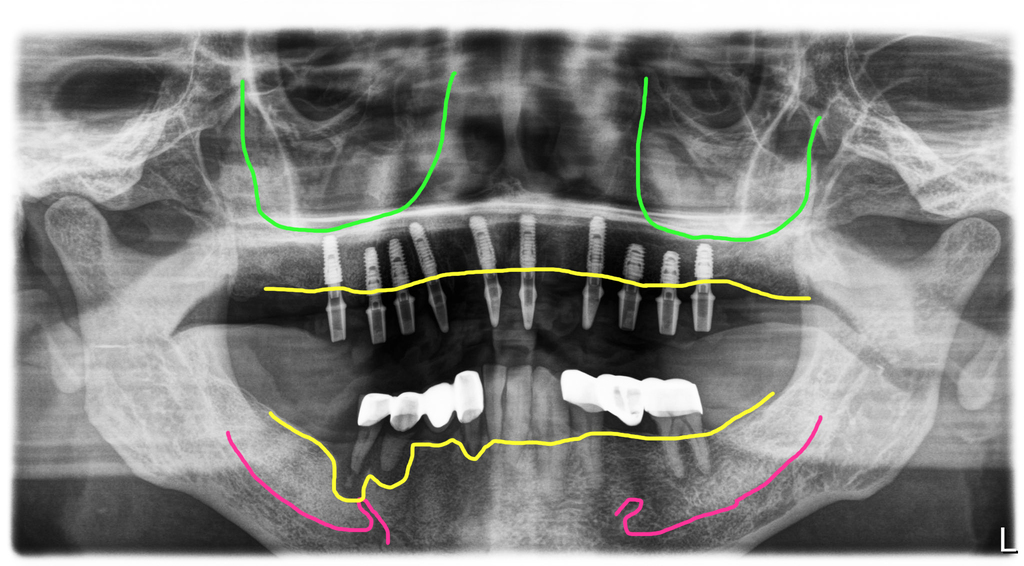

왼쪽 위에 치아가 여러개 없지만 오른쪽으로 계속 드시면서 치료를 미루고 계셨던 분입니다. 치아상태가 좋지 않다는 것은 알았지만 치아뿌리 속의 상태나 뼈의 상태는 환자는 알 수가 없잖아요. 오른쪽 마져 이제 씹는 것이 힘들어져서 전체적으로 치료를 하러 오셔서 파노라마 엑스레이를 찍었습니다.

위쪽에 남아있는 치아들도 치조골이 거의 녹아서 장기간 버틸 수 없는 상태였고, 아래쪽은 오른쪽에는 작은어금니 부위에 염증이 너무 심하게 진행되어 턱뼈가 아주 심하게 파괴되어 있었습니다.

이렇게 빨강색 선인 신경까지 염증(노랑색선)이 진행되어 해당 부위에는 임플란트를 식립할 수가 없는 상태였습니다. 억지로 심게 되면 신경손상 가능성이 아주 높아집니다.